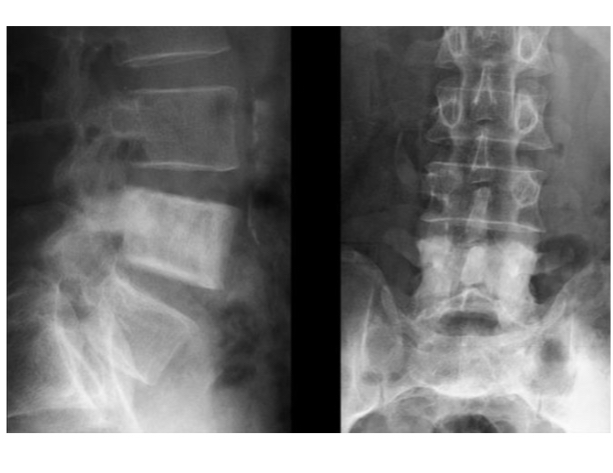

Spondyloarthrite ankylosante

syndesmophytes à plusieurs étages

Aspects de « colonne bambou »